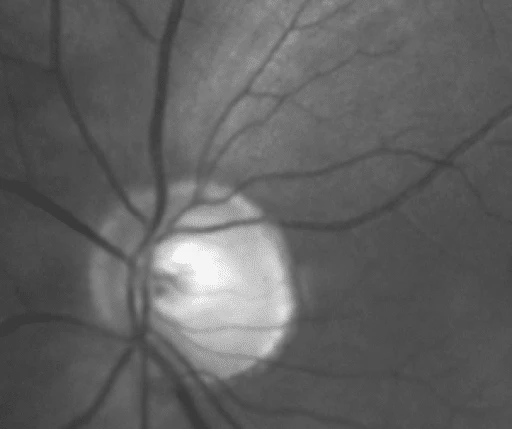

Et digitalt bilde kan blant annet gi hint om rimmen er blitt fortynnet, om blodkar er blitt forflyttet (bilde 5-6)og om det er en splinthemorragi på rimmen (bilde 2). For å få en god og presis mulighet til å bestemme ekskavasjonen, trengs et 3Dblikk med forstørrelse.

Glaukom skal alltid ha med seg både optisk nervehode (ONH) rim fortynning og retinal nervefiber ( RNFL) fortynning ( bilde 1). Hvis ikke – er ikke diagnosen Glaukom tilfredsstilt!

Både ONH rim og RNFL observeres lettest i rødfri belysning på et øyebunnscan (Bilde 1,3 og 4). Rimmens farge, størrelse og form beskrives. En grå ONH er vanligvis ikke tilhørende glaukom Dx. Området der det skal forventes en fortynning er temporalt superior og temporalt inferior med utfall av RNFL, tilhørende dette området.

Bilde 1 RNFL pga rim fortynning dvs Glaukom ( Rødfritt)

Bilde 2 Splint hemorragi over rim og utover på retina

Bilde 5 og 6 viser rim fortynning OS superior /temporalt med forflytning av arterie og RNFL

utfall og en periode på 7 år.